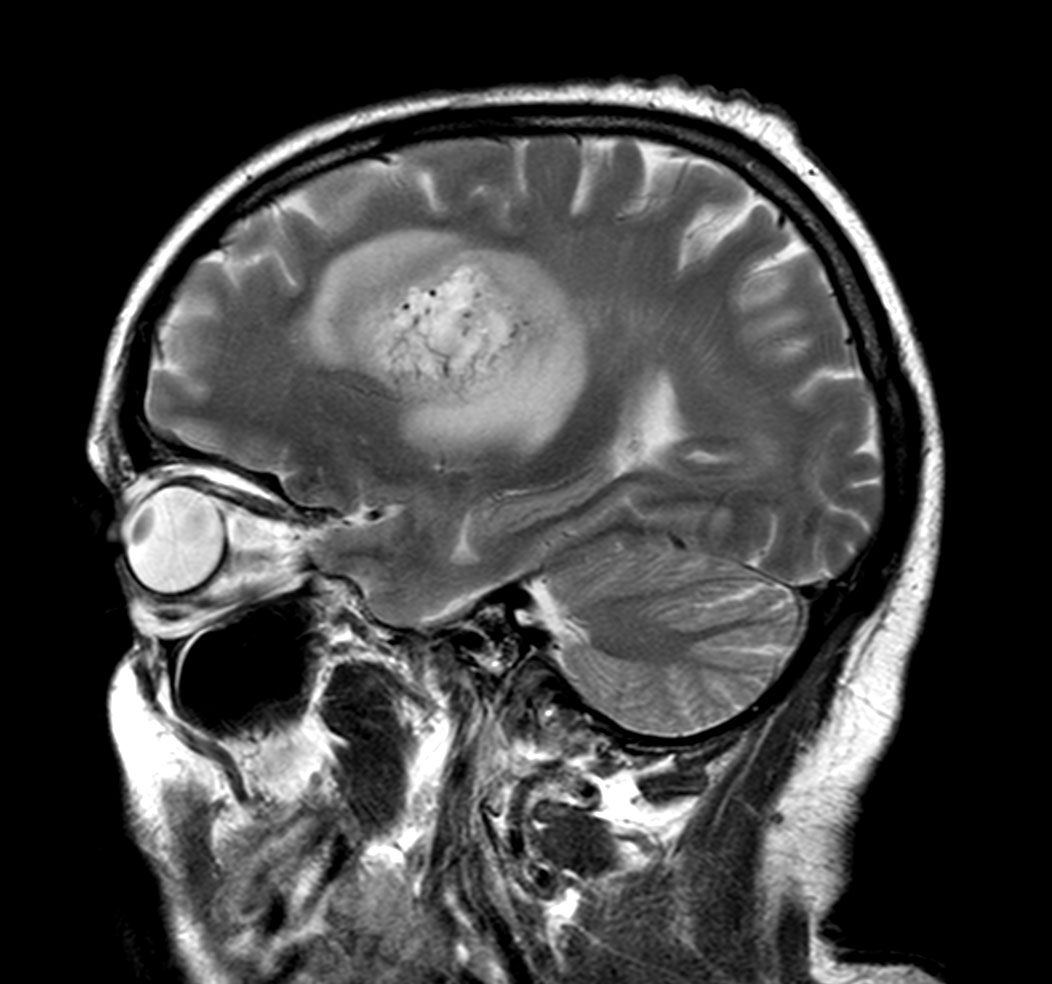

Sagittal T2w TSE